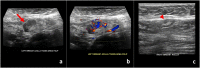

With the recent U.S. Food and Drug Administration (FDA)-approval and rollout of the Pfizer-BioNTech and Moderna COVID-19 vaccines, it is important for radiologists to consider recent COVID-19 vaccination history as a possible differential diagnosis for patients with unilateral axillary adenopathy. Hyperplastic axillary nodes can be seen on sonography after any vaccination but are more common after a vaccine that evokes a strong immune response, such as the COVID-19 vaccine. As the differential of unilateral axillary adenopathy includes breast malignancy, it is crucial to both thoroughly evaluate the breast for primary malignancy and to elicit history of recent vaccination. As COVID-19 vaccines will soon be available to a larger patient population, radiologists should be familiar with the imaging features of COVID-19 vaccine induced hyperplastic adenopathy and its inclusion in a differential for unilateral axillary adenopathy. Short-term follow-up for unilateral axillary adenopathy in the setting of recent COVID-19 vaccination is an appropriate recommendation, in lieu of immediately performing potentially unnecessary and costly axillary lymph node biopsies.